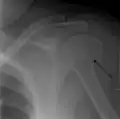

A fracture of the greater tuberosity as seen on AP X ray

A fracture of the greater tuberosity of the humerus